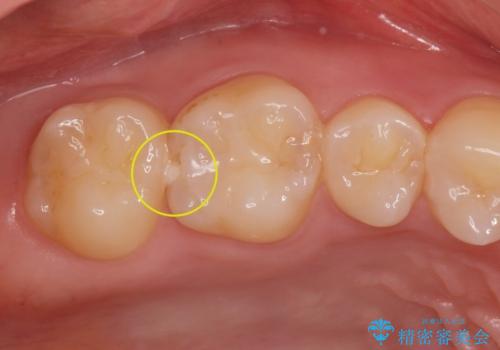

- 銀歯をやりかえたいが他院で抜歯と言われセカンドオピニオンで来院。適合の悪い被せ物が入っており、まずは古い材料、虫歯をとり保存可能か確かめる必要があり、拡大鏡下で全て取り除いたら歯質が歯茎の中まで虫歯がありました。このまま無理やり型取りをして被せ物を作っても不適合な被せ物が入る可能性が高いため歯茎を切り取る手術(ディスタルウェッジ)を行いました。そして再根管治療を行いゴールドの被せ物で治療を行いました。

適合の良い被せ物が入り大変満足して頂けました。